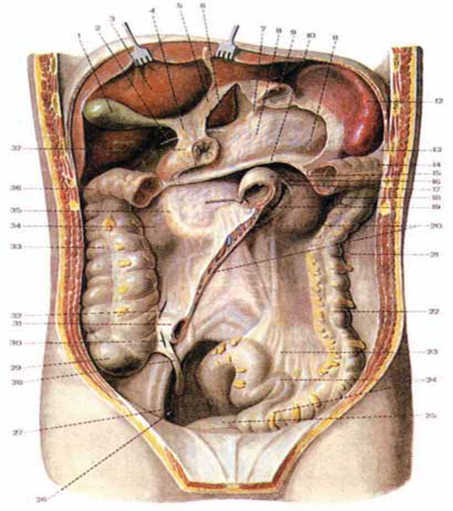

Анатомия малого таза: детальные схемы и изображения